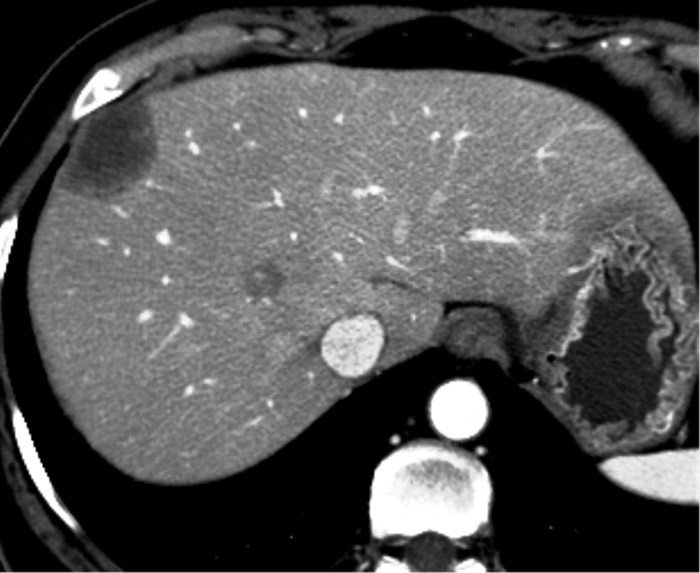

- Diaqnozu dəqiqləşdirmək üçün Qc venaları yoxlanılmalıdır. Bunun üçün dopler USM, KT-angioqrafiya, MRT-angioqrafiyalar və ya kontrastlı venoqrafiya edilir.

- Görüntüləmədə Qc venalarının trombotik tutulması diaqnozu dəqiqləşdirən əlamətdir.

PVT diaqnozunu dəqiqləşdirmək üçün portoqrafiya aparılır – Doppler USM, KT və ya MRT angioqrafiya.

- Kontrastlı müayinələrdə damarda tromb və ya kavernoz transformasiya

Baddi-Kiari sindromu böyük qaraciyər venalarının tıxanması nəticəsində meydana gələn venoz durğunluqdur, qaraciyər venaları ilə yanaşı aşağı boş venada da tıxanma ola bilir. Tromboz, fibroz, membran və infiltrasiya (şişlər, iltihab) ən çox rast gələn səbəbləridr. Erkən mərhələlərdə kəskin hepatit və kəskin qaraciyər yetməzliyi, xroniki mərhələdə sirroz və PH meydana gələ bilir. Diaqnozu üçün tomoqrafiya və kontrastlı angioqrafiya lazım gəlir, Qc venalarının trombotik tutulması diaqnozu təsdiqləyir. digər xarakterik əlaməti birinci seqmentin hipertrofiyasıdır. Erkən mərhələdə dekompressiya (cərrahi və stend) sirroz əmələ gəldikdə isə transplantasiya ön planda tutulur.

Qaraciyər venalarının görünməməsi, kontrastlaşmaması və ya trombla tıxanması.